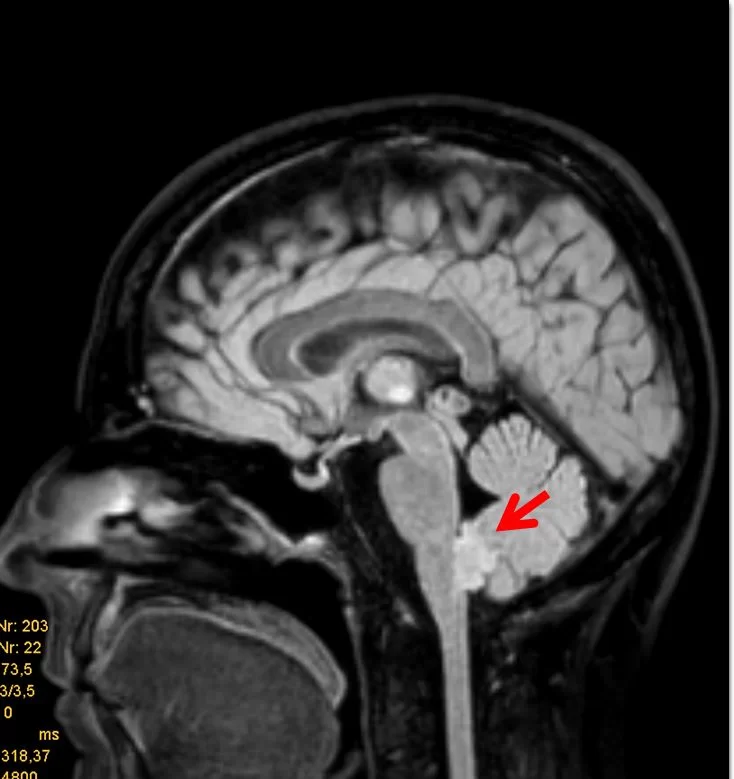

Τα επενδυμώματα ανήκουν στα γλοιώματα και αναπτύσσονται τυπικά εντός ή πλησίον του επενδύματος του κοιλιακού συστήματος του εγκεφάλου. Η πιο συνηθισμένη θέση είναι η περιοχή της παρεγκεφαλίδας (Εικόνα 1 & 2).

Τα ενδοκρανιακά επενδυμώματα παρουσιάζουν μέγιστη επίπτωση στην παιδική ηλικία, με μέση ηλικία διάγνωσης τα πέντε έτη. Στους ενήλικες, τα επενδυμώματα είναι πιο συχνά στην περιοχή του νωτιαίου μυελού.